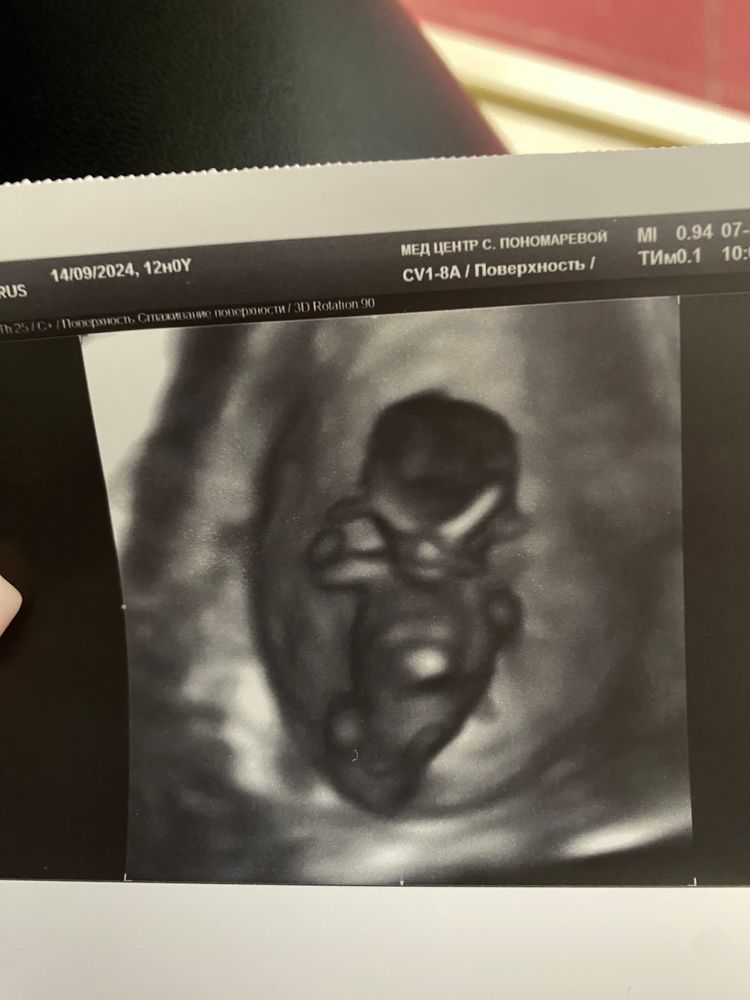

Гадаем по половому бугорку)))

Как думаете кто?❤️💙 1 скрининг